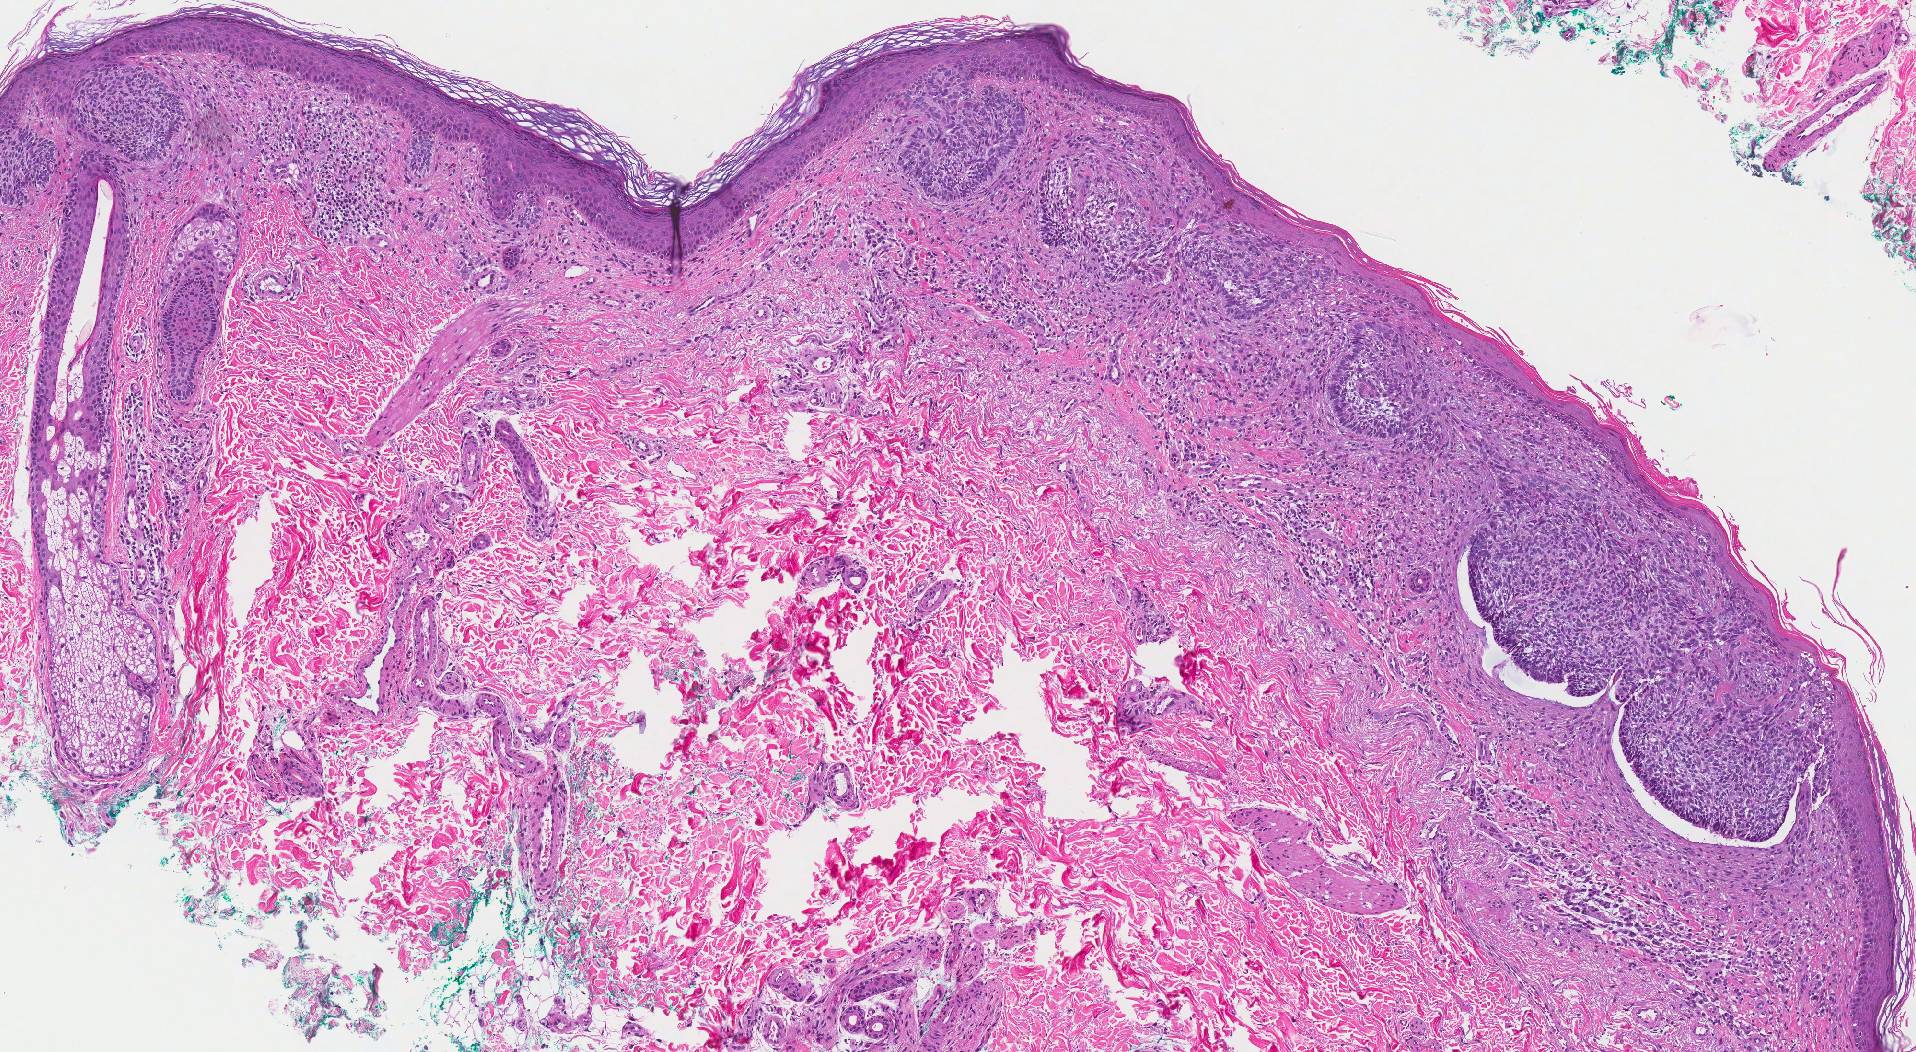

Клетки, участващи в рак на кожата​

Ракът на кожата започва в най-горния слой на кожата – епидермиса. Епидермисът е тънък слой, който осигурява защитно покритие от кожни клетки, които тялото ви непрекъснато отделя. Епидермисът съдържа три основни типа клетки:

• Сквамозните клетки се намират точно под външната повърхност и функционират като вътрешна обвивка на кожата.

• Базалните клетки, които произвеждат нови кожни клетки, се намират под сквамозните клетки.

• Меланоцитите - които произвеждат меланин, пигментът, който придава нормалния цвят на кожата - се намират в долната част на епидермиса. Меланоцитите произвеждат повече меланин, когато сте на слънце, за да предпазите по-дълбоките слоеве на кожата си.

Къде започва вашият рак на кожата определя неговия тип и вашите възможности за лечение.